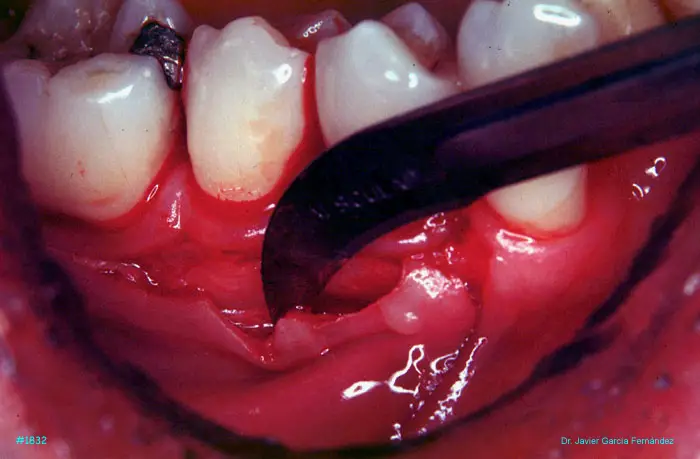

Atlas of Surgical Techniques in Periodontics. CASOS CLINICOS.

Atlas de Técnicas Quirúrgicas en Periodoncia

image 98